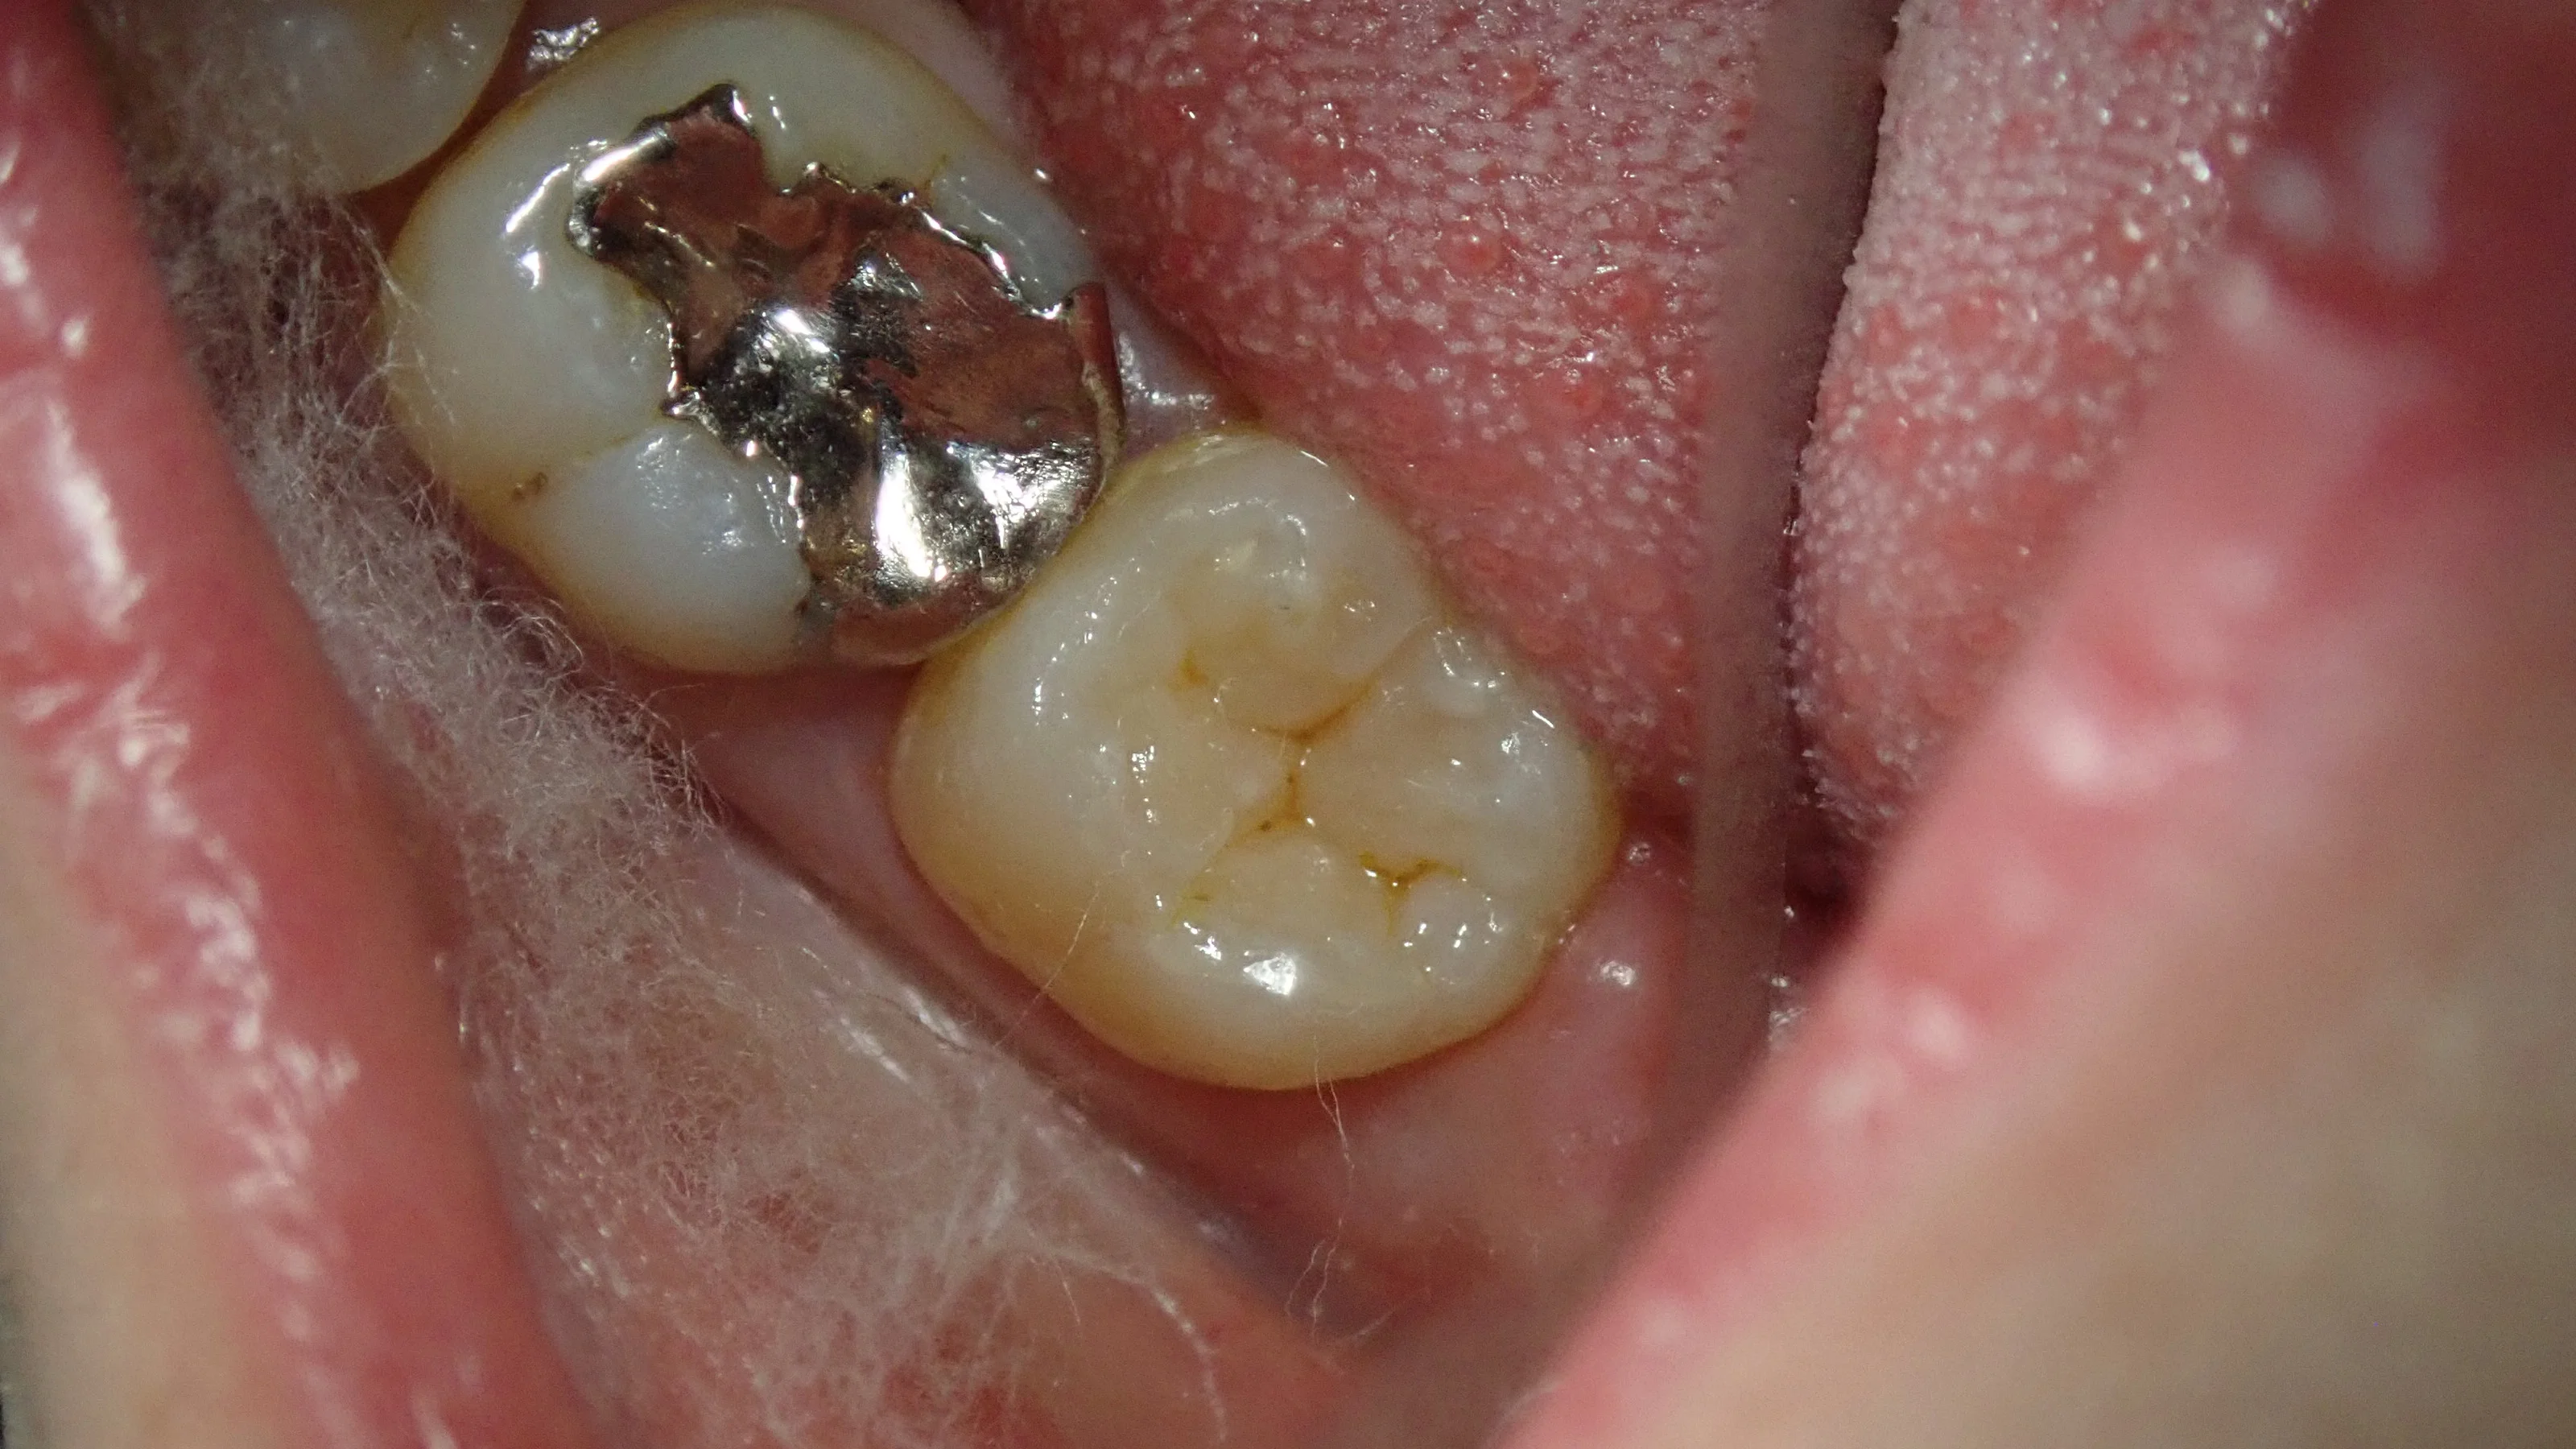

術前がこちら

手前の歯との間は矯正の後戻りによって隙間が開いている状況になっています。

金属を軽くとったのがこちらですね。